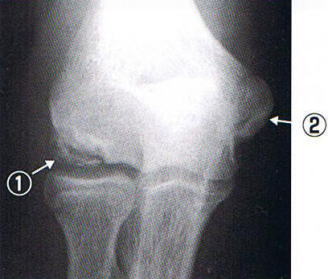

レントゲン像

@ 骨の不整像

A 成長軟骨の異常